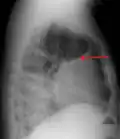

A pleural effusion appears as an area of whiteness on a standard posteroanterior chest X-ray.[15] Normally, the space between the visceral pleura and the parietal pleura cannot be seen. A pleural effusion infiltrates the space between these layers. Because the pleural effusion has a density similar to water, it can be seen on radiographs. Since the effusion has greater density than the rest of the lung, it gravitates towards the lower portions of the pleural cavity. The pleural effusion behaves according to basic fluid dynamics, conforming to the shape of pleural space, which is determined by the lung and chest wall. If the pleural space contains both air and fluid, then an air-fluid level that is horizontal will be present, instead of conforming to the lung space.[16] Chest radiographs in the lateral decubitus position (with the patient lying on the side of the pleural effusion) are more sensitive and can detect as little as 50 mL of fluid. Between 250 and 600mL of fluid must be present before upright chest X-rays can detect a pleural effusion (e.g., blunted costophrenic angles).[17]

Chest computed tomography is more accurate for diagnosis and may be obtained to better characterize the presence, size, and characteristics of a pleural effusion. Lung ultrasound, nearly as accurate as CT and more accurate than chest X-ray, is increasingly being used at the point of care to diagnose pleural effusions, with the advantage that it is a safe, dynamic, and repeatable imaging modality.[18] To increase diagnostic accuracy of detection of pleural effusion sonographically, markers such as boomerang and VIP signs can be utilized.[19]

A pleural effusion as seen on lateral upright chest x-ray -

Pleural effusion as seen behind the heart.[20]